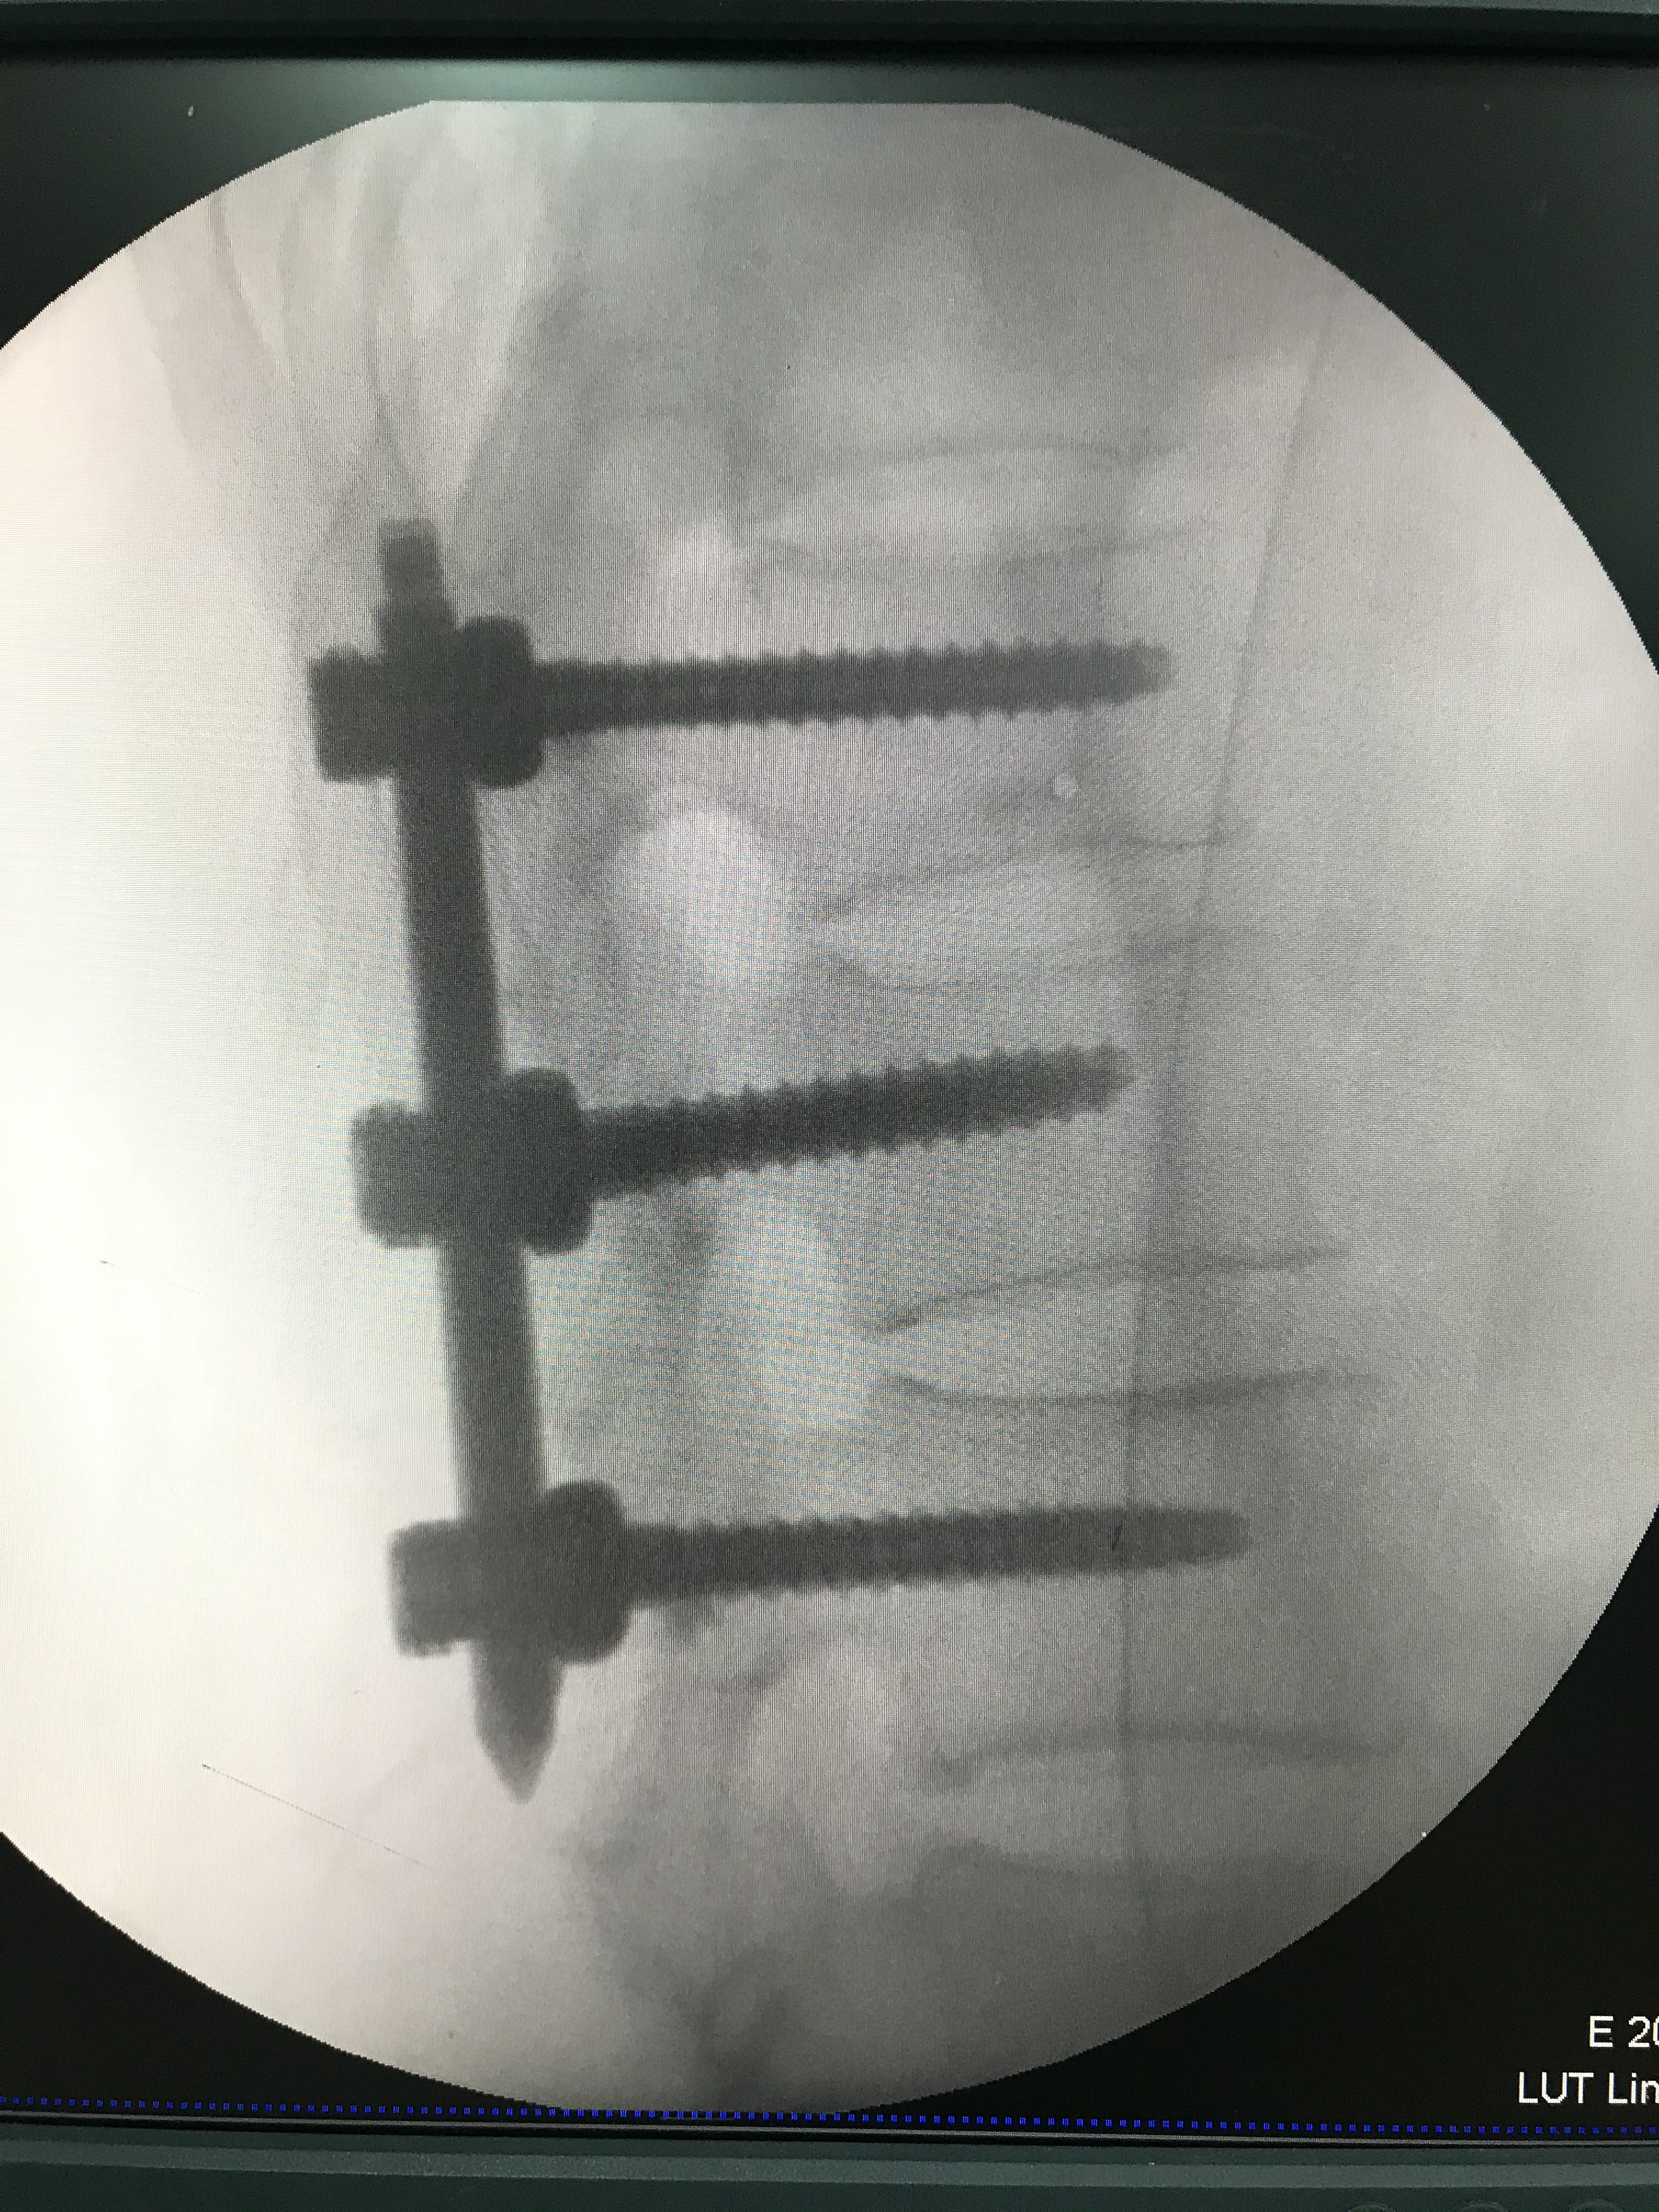

市一院骨六科完成经皮椎弓根钉棒内固定术治疗腰椎压缩性骨折一例

图片尺寸1595x1591